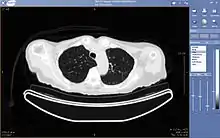

Teleradiology is the ability to send radiographic images (x-rays, CT, MR, PET/CT, SPECT/CT, MG, US...) from one location to another.[76] For this process to be implemented, three essential components are required, an image sending station, a transmission network, and a receiving-image review station. The most typical implementation are two computers connected via the Internet. The computer at the receiving end will need to have a high-quality display screen that has been tested and cleared for clinical purposes. Sometimes the receiving computer will have a printer so that images can be printed for convenience.

The teleradiology process begins at the image sending station. The radiographic image and a modem or other connection are required for this first step. The image is scanned and then sent via the network connection to the receiving computer.

Today's high-speed broadband based Internet enables the use of new technologies for teleradiology: the image reviewer can now have access to distant servers in order to view an exam. Therefore, they do not need particular workstations to view the images; a standard personal computer (PC) and digital subscriber line (DSL) connection is enough to reach Keosys' central server. No particular software is necessary on the PC and the images can be reached from anywhere in the world.

Teleradiology is the most popular use for telemedicine and accounts for at least 50% of all telemedicine usage.